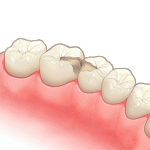

②虫歯を削り型取りします

-

③インレーを入れます